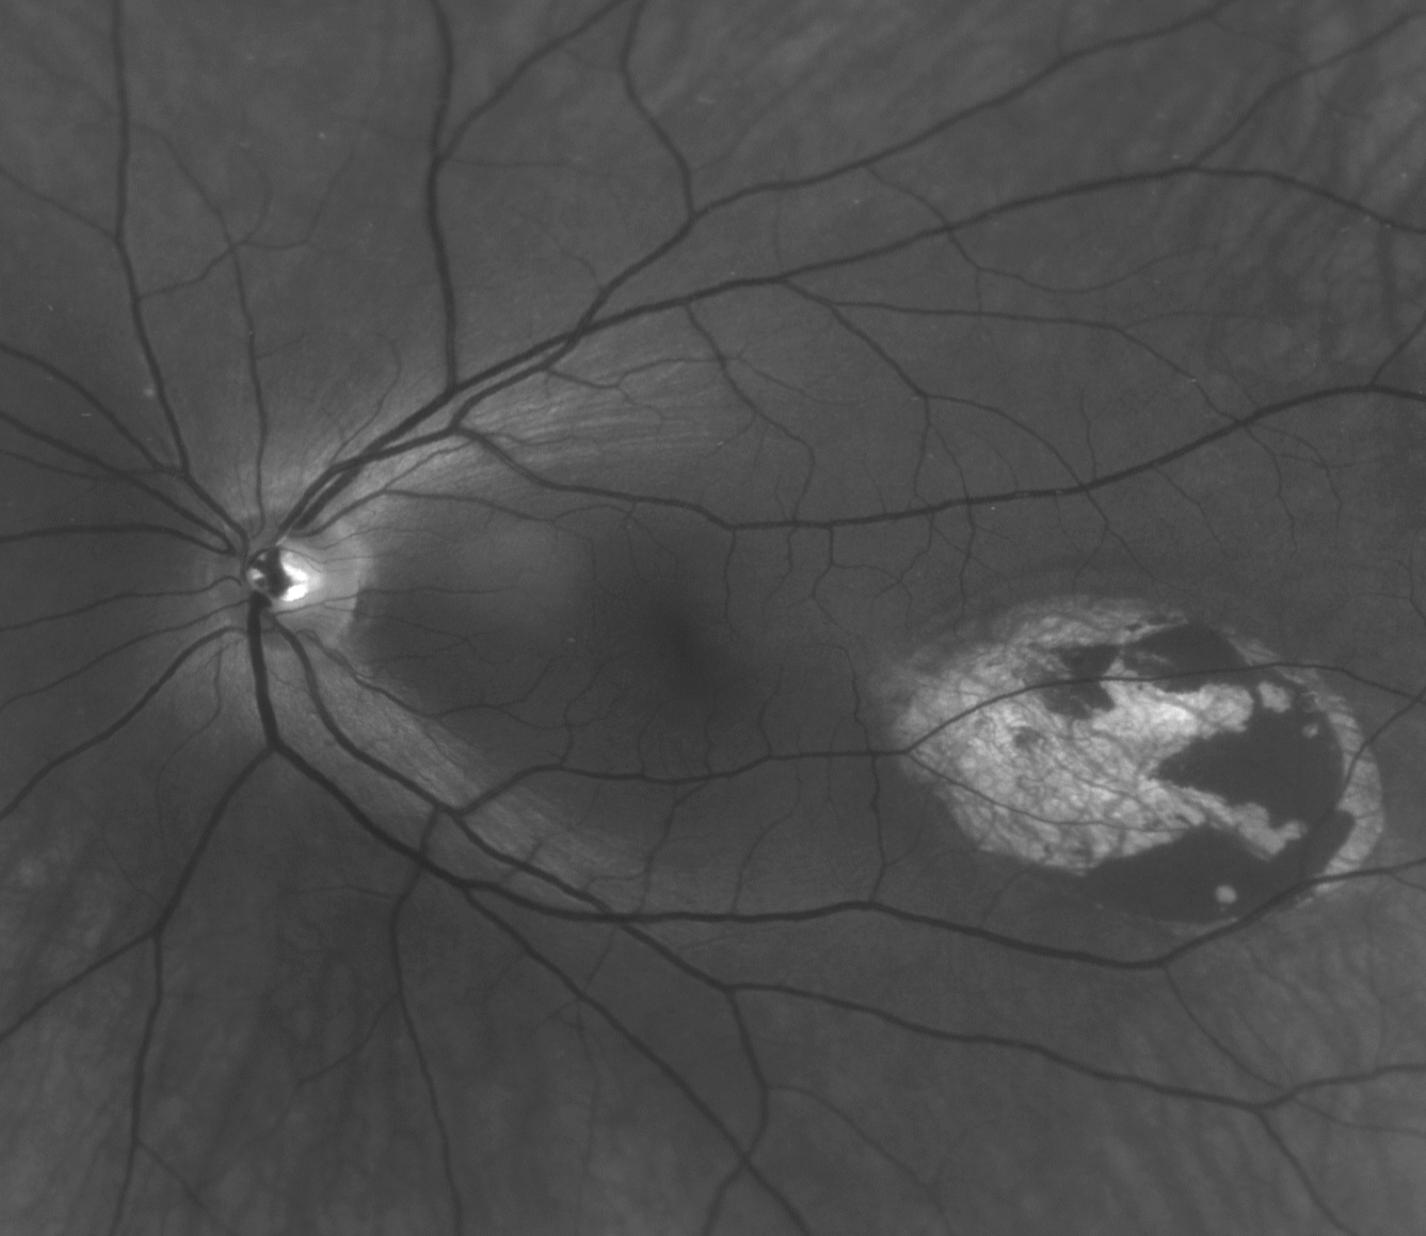

Ocular toxoplasmosis is an infection in the eye caused by the parasite Toxoplasma Gondii. A common retinal finding in its inactive stages are pigmented retinochoroidal scarring. The retinal function in the affected area assumingly reflects the amount of retinal involvement. This case report presents a 48-year-old woman who has a long-standing large retinochoroidal scar in the temporal posterior pole of her left eye. She had not experienced any visual symptoms, and no recurrent infections had occurred as far as she knew. She has a scotoma in her nasal visual field that her optometrist detected by a coincidence when she was in her twenties. The corresponding visual field defect is smaller and less deep than what may be expected from the structural appearance of the scar. The reported case demonstrates, that the visual function may be well preserved in the visual field corresponding to a retinochoroidal scarred area due to toxoplasmosis, in spite of loss of structures in the outer retinal layers as seen with OCT.